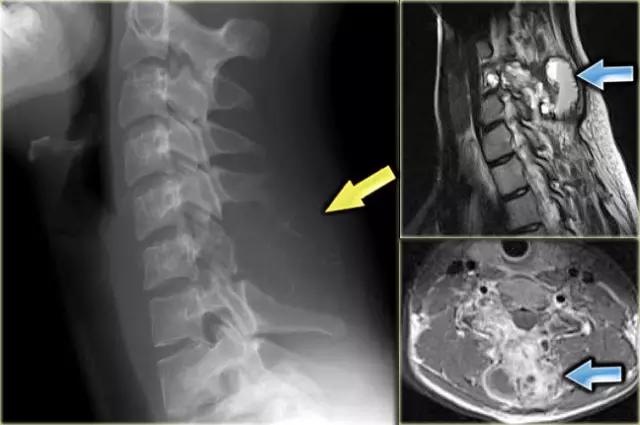

另一个GCT表现为边界欠清晰的病灶,从C5和C6棘突所产生的一个周边骨壳膨胀性病变。具有FS的矢状T2加权MR图像显示肿瘤内的多个小腔,是继发性ABC。